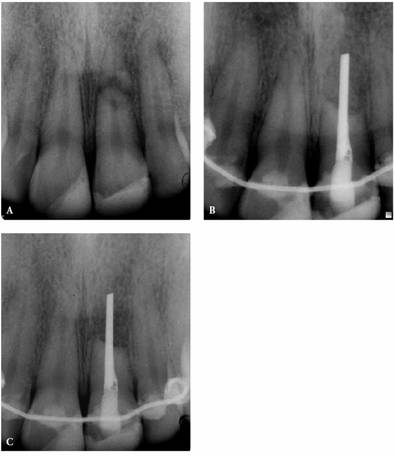

angulations of the suspected tooth (Figures 19-24A

and B).

Comparing varied views is essential in diagnosing the presence of additional

roots, anatomic configurations, anomalies, and other unusual circumstances that

may complicate the treatment.

Figure 19-24A and B: (A) Pretreatment radiograph of a mandibular premolar shows one canal. (B) A second radiograph taken from an angulation of 15 degrees from the mesial discloses a second root.